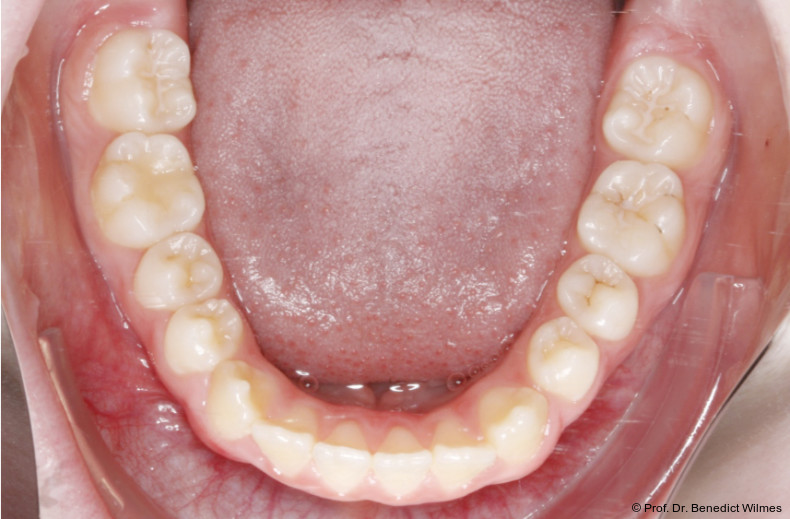

Eine 13-jährige Patientin stellte sich mit beidseitigem Kreuzbiss, einem anterioren offenen Biss und einer Angle Klasse II vor. Das viszerale Schluckmuster wurde mittels logopädischer Maßnahmen umgestellt, der offene Biss persistierte jedoch (Abb. 3a–l).